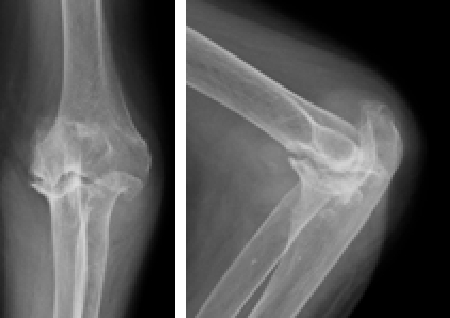

術前

左肘関節の変形を認めます

術後

人工関節して痛みや可動域が改善しました